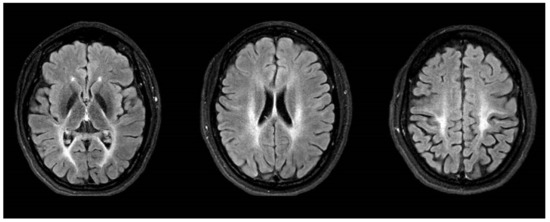

| MRI abnormalities | Leukencephalopathy | none | Normal: 6/20 Cerebellar atrophy: 11/20 Leukencephalopathie: 3/20 |